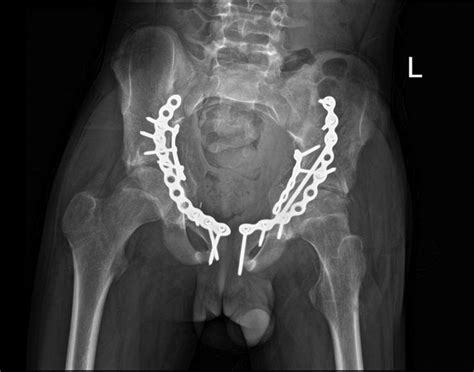

The term Open Reduction And Internal Fixation describes two distinct parts of a surgical process. "Open reduction" refers to the surgeon making an incision to access the bone directly and reposition the fractured segments so they align properly. "Internal fixation" refers to the method of holding the bone in place using specialized medical hardware, such as metal plates, screws, pins, or rods.

- Fixation: Once aligned, the surgeon attaches hardware to stabilize the fragments. This might involve placing a titanium or stainless steel plate across the break and securing it with small screws.

⚠️ Note: The type of hardware used—whether it is a plate, screw, or intramedullary nail—depends heavily on the specific bone affected and the nature of the fracture pattern.